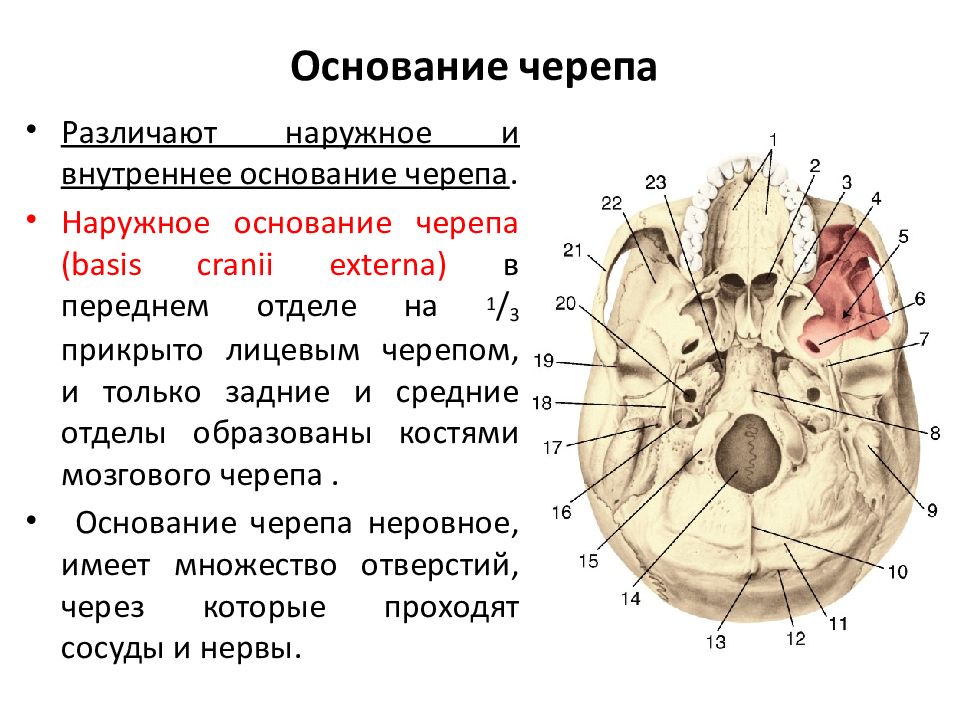

Анатомические детали: Фотографии топографии черепа с нижнего вида

Раздел: Альбом идей